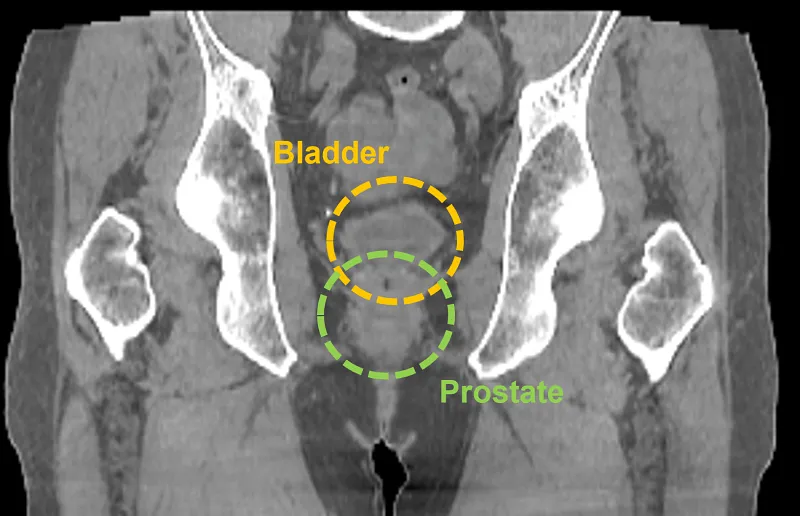

Prostate

In this prostate case, the larger FOV provided by the HyperSight image, taken using a Varian TrueBeam system, enables a clinician to see the entire treatment area including the lymphatic region, which may also require treatment. It also enables the clinician to visualize the relevant anatomy without acquiring multiple CBCT images.

Hypersight prostate

Image courtesy of University Hospitals Seidman Cancer Center, Cleveland, Ohio.